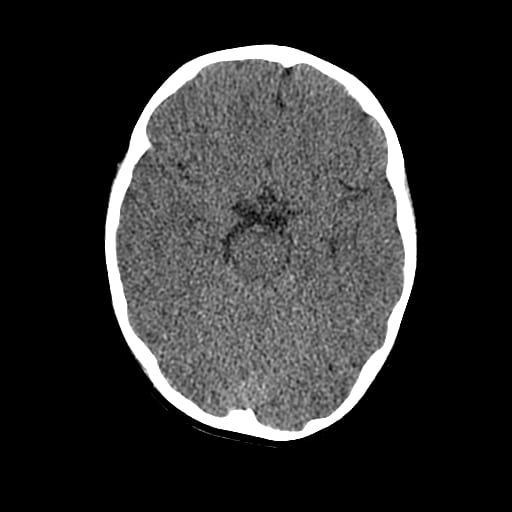

Age: 1

Sex: Male

Indication: Fall